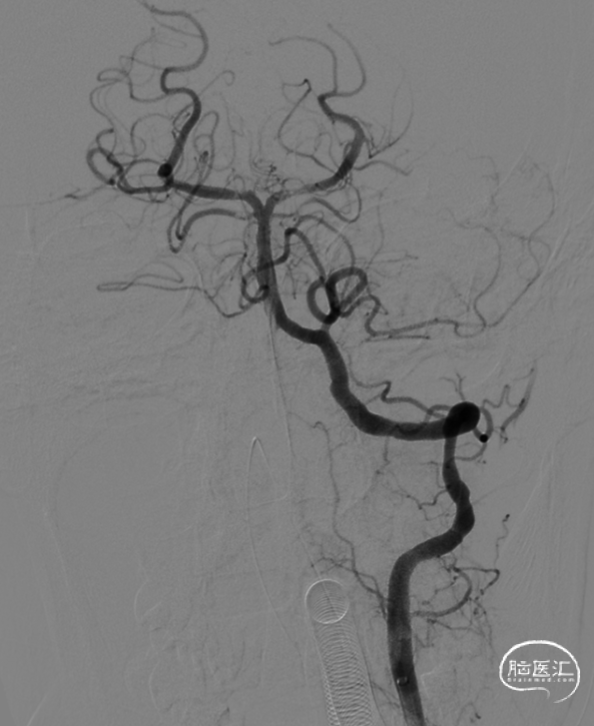

术前CTA:基底动脉顶端闭塞。

左侧椎动脉造影。

负压抽吸2次,基底动脉顶端部分再通,见栓子向双侧大脑后动脉逃逸。

左侧大脑后动脉P1段发白,观察20min较前好转,血流状态维持良好,结束手术。